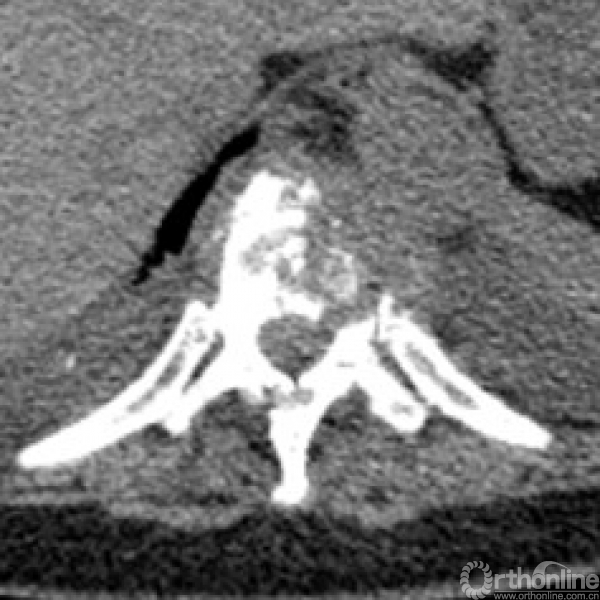

胸椎多椎体病变,如果诊断和治疗?